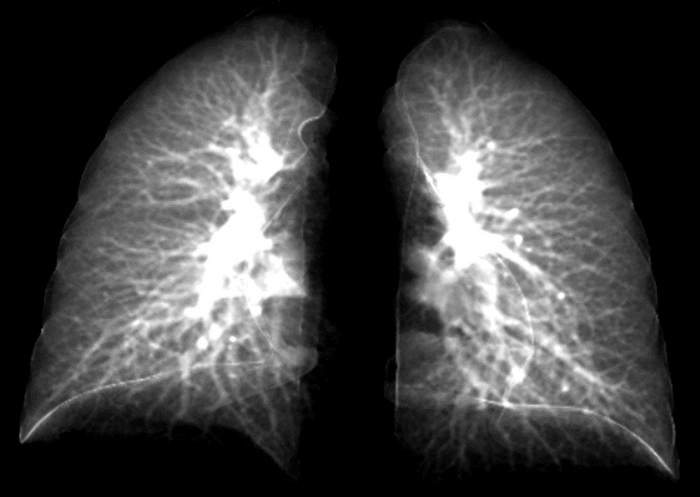

For patients dealing with lingering respiratory symptoms from the novel coronavirus, a chest X-ray can reveal only so much. The two-dimensional (2D) scans simply can’t distinguish compromised lung function. For that diagnosis, a more expensive, three-dimensional (3D) technique called a CT scan is necessary.

That may change. In a new study, researchers at the University of Iowa have developed what is called a contrastive learning model. This model “learns” from composite 2D images constructed from 3D CT images to detect compromised lung function in long-COVID patients. Another technique, called transfer learning, then conveys lung diagnostic information from a CT scan to a chest X-ray, thus allowing chest X-ray equipment to detect abnormalities the same as if those patients had used a CT scan.

In the study, the researchers showed how their contrastive learning model could be applied to detect small airways disease, which is an early stage of compromised lung function in long-COVID patients. Of the long-COVID patients, the models were advanced enough to distinguish the severity of the compromised lung function, separating those with small airways disease from those with more advanced respiratory issues.

Small airways disease affects a network of more than 10,000 tubes at the nexus in the lung where oxygenated air mixes with blood to be carried throughout the body. People with small airways disease have many of these vessels constricted, thus limiting the oxygen-blood exchange in the lungs, and impeding breathing overall.

IMAGE CREDIT: Ching-Long Lin lab, University of Iowa